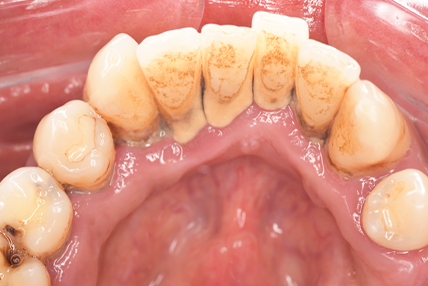

CASE 3

Before

After

基本情報

| 年齢・性別 | 30代・女性 |

| 主訴 | 定期検診 |

| 治療内容 | PMTC |

| 治療期間 | 60分 |

| 治療費 | 5,750円 |

| リスク・副作用 | しみる可能性があります。 |

| 治療方針 | PMTCでステインの除去。 |

| 担当者所見 | ステインが付きやすいため、3カ月毎の定期検診で除去する。 |